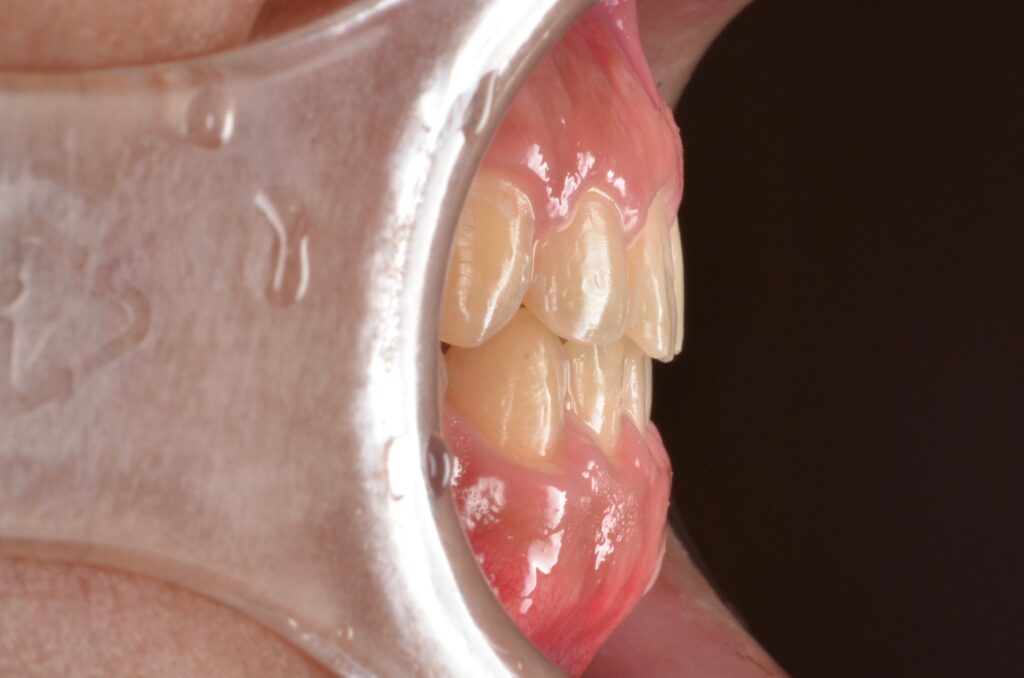

大学病院で顎の手術が必要と診断された20代男性の受け口を、ワイヤー矯正のみで治療した症例です。外科手術や抜歯は行わず、2年間かけて反対咬合を改善。事前の精密な診断が、的確な判断へと導きました。

| リスク・副作用 | リテーナーの不使用による矯正治療の後戻り |

|---|---|

| 費用 | 約125万円 (税別) |

| 期間 | 2年 |